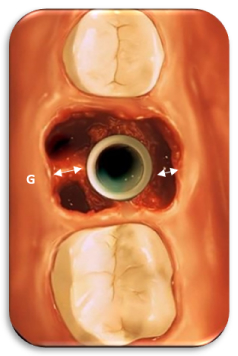

Voids around the implant and the bone lead to resorption if the gap is large and the tissue biotype is thin; the use of bone grafts in the aesthetic zone and in the posterior areas manipulate the bone by gentle

maneuvering or compaction of bone with bone molders or gently tapping the bone with chisels towards the implant. This technique may not only close the voids but also will significantly enhance the densification of bone and increases the primary stability of the implant.

The implant should be, all around the interradicular bone. Spontaneous healing & osseointegration is more favorable if the Implants placed have a Jumping gap –G, [18] of less than 2mm 7. If the gap between the implant and the bone is more than 2 mm then the author strongly recommends using platelet-rich fibrin, barrier membrane, or bone grafts to facilitate bone formation and obliterate the epithelial ingrowth.